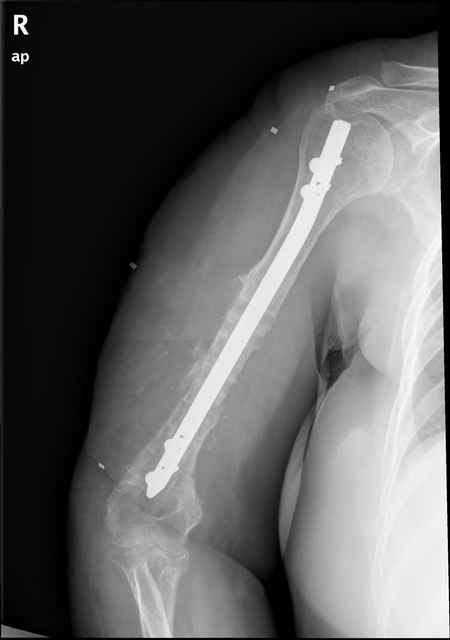

Больная 48 лет, медсестра-массажист, перелом плеча 7 лет назад, оперирована 4-кратно и безуспешно

Больная 48 лет, медсестра. Травма получена 7 лет назад, оперирована первично в Турции - остеосинтез пластиной - несращение - реостеосинтез стержнем там же через год (обычным, с выстоянеием его в полость плеча) - несращение - поступила к нам впервые в марте 2008 года - удаление стержня, реостеосинтез пластиной и костная пластика, в течение 2 лет лизис кости вокруг винтов, смещение фиксатора, в марте 2010 - удаление пластины, реостеосинтез интрамедуллярным стержнем с блокированием (рассверливание + костная пластика). В динамике - вновь лизис в области перелома, нестабильность дистальных блокирующих винтов.

Уважаемый коллега. Ось и длина конечности сохранены. Фиксация, согласно снимков, стабильная. Проводить дополнительные операции считаю нецелесооразным. Можно применить бифосфонаты, желательно 1-2 поколения (бонефос), в\в в условиях интенсивной терапии, они довольно агрессивно и быстро кальцинируют именно остеопоротичную кость, желательно проконсультироватся с коллегами онкологами у которых есть опыт применения. Бифосфонаты 3-4 поколения можно давать годами с увеличением костной массы на 3-5% в год.

Клинически фиксация пока действительно стабильна, но на рентгенограммах резорбция кости в области дистальных блокирующих винтов и миграция одного из них.